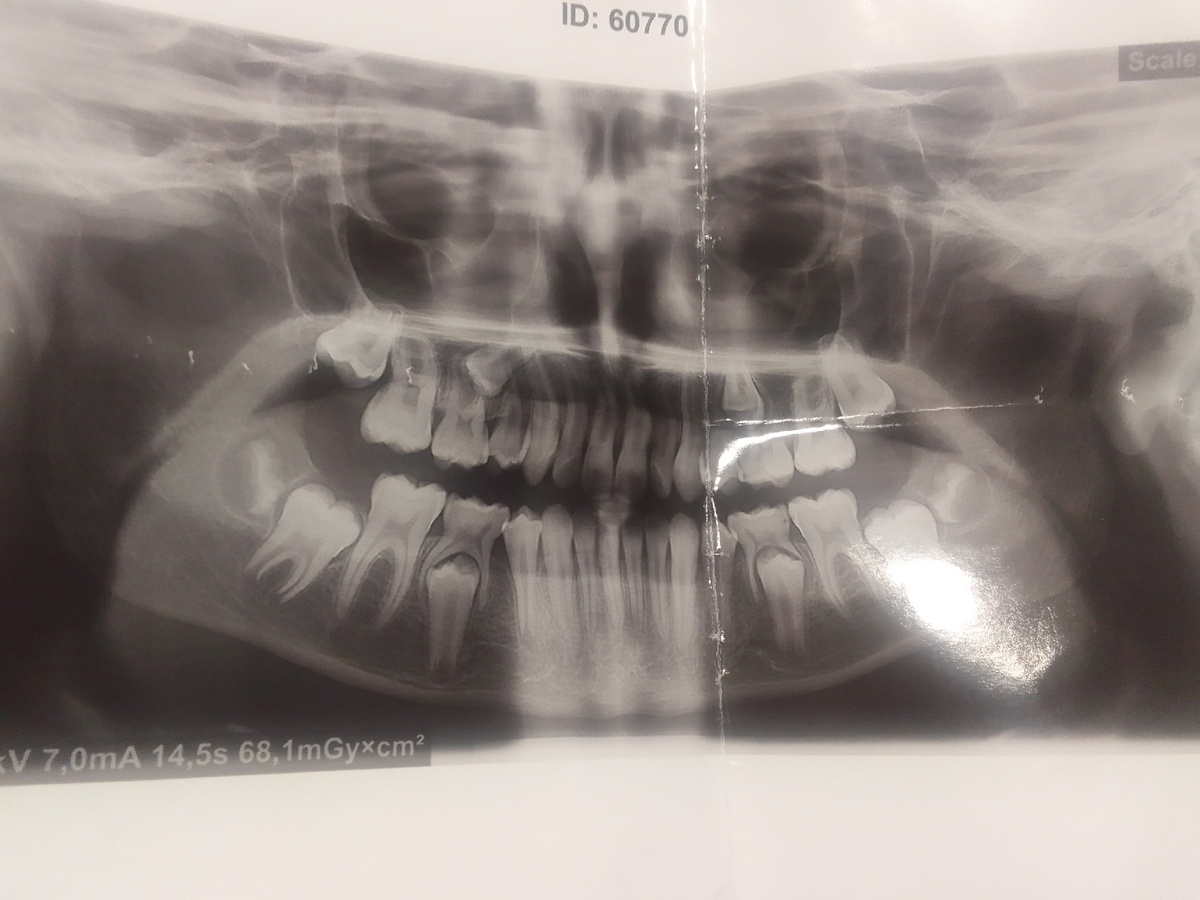

Делать нечего, пришлось идти. Ортодонт направил на снимок. Смотрит снимок:

- Нууу... Тут у неё зуб в зубе, понимаете?

- Это когда молочные крепкие и не выпали, а коренные уже полностью сформировались. Вам нужно срочно удалять все 4 зуба, иначе коренные будут потихоньку рассасываться в десне.

Зуб в зубе. Не ребёнок, а акуленок какой-то.

Как подрастут коренные, будем устанавливать брекеты. По снимку уже понятно, что вылезут они в разные стороны. На брекеты уже сейчас можно начинать копить))